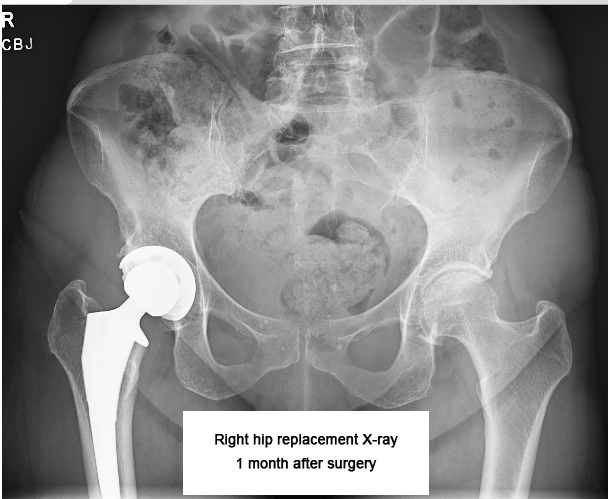

April 10 was a telehealth call with Dr. Martin to review my recent x-rays. He said everything looks great and is healing very well, so he said I can start ramping up my activity level. Great news!

Our appointment at the Joint Replacement Center of Scottsdale started with an assessment and discussion with Dr. Martin’s surgery coordinator. She thought the incision and amount of swelling looked good, but she was conservative with her outlook on when I could resume driving and swimming (the original thought that I shouldn’t swim until 6 weeks after surgery). However, after examining me, Dr. Martin said he was delighted with my progress and said I was good to resume both driving and swimming. YAY!! He said that the pain in my inner thigh was muscular, most likely from the new exercises I was doing: supine straight leg lifts and standing knee lifts. Too soon to do those — he said to take a couple of easy days. Otherwise, everything looked great and we booked our next follow up for mid April, at which point he would review X-rays of my hips to see how the new joint is healing.